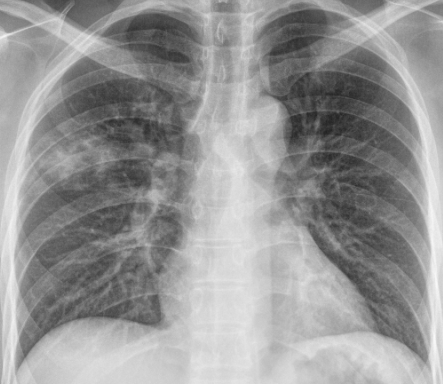

病史:29 岁女性,既往体健。主因「发热 13 天,咳嗽、咳痰 10 天,胸痛 4 天」入院。患者 13 天前无明显诱因出现发热,体温高达 40℃,伴畏寒,3 天后出现咳嗽、咳痰,夜间为甚,伴有解稀水样大便。于当地医院退热、抗炎对症支持治疗,无明显改善;3 天前患者出现左侧胸痛,咳嗽、左侧卧位等动作时疼痛加剧,至我院急诊科查胸部 X 线提示「双肺肺炎」(图 1)。

图 1 胸部 X 线